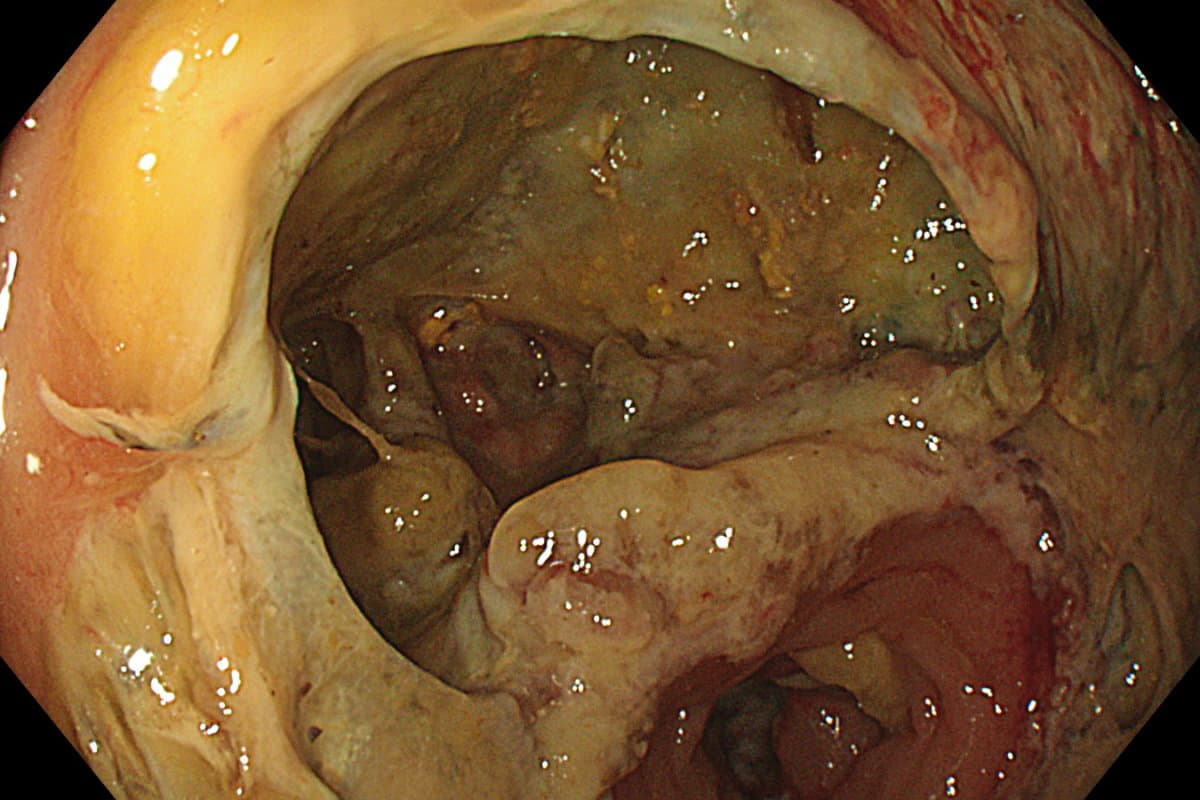

Eine Refluxdrainage verhindert die Anastomoseninsuffizienz bei abdominothorakaler Ösophagusresektion.

Wenn sich Malignome am gastroösophagealen Übergang operativ behandeln lassen, ist die abdominothorakale Ösophagusresektion das Verfahren der Wahl. Bei dieser Technik wird ein Schlauchmagen gebildet und im Thorax mit dem oralen Teil der Speiseröhre verbunden (Ivor-Lewis-Ösophagektomie).

Allerdings ist der Eingriff mit einer hohen Morbidität und Mortalität verbunden. Denn es drohen postoperative Heilungsstörungen im Bereich der Anastomose.